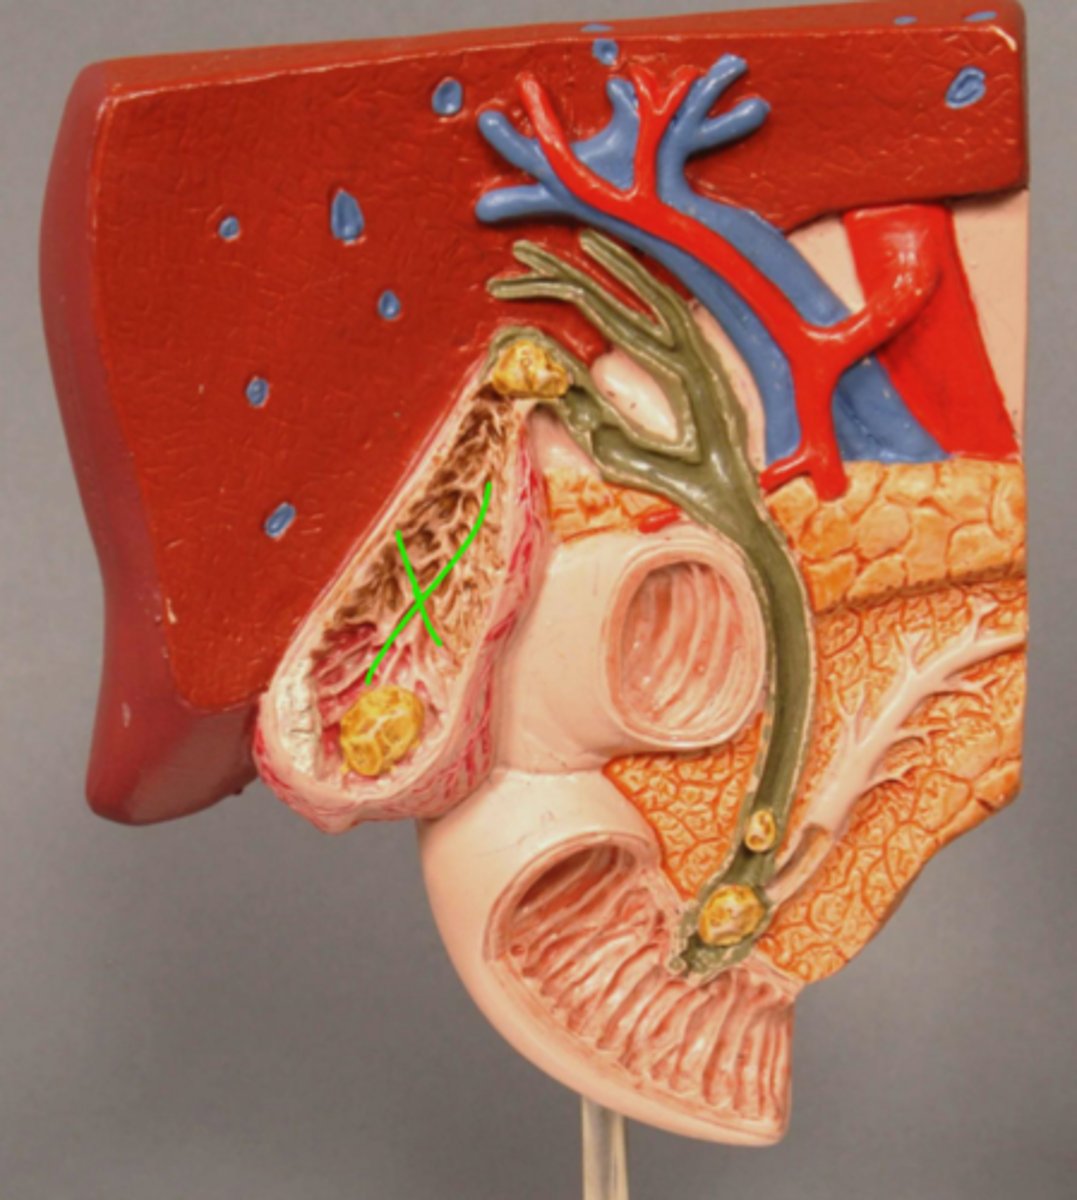

Gallbladder Mucosa

Gallstone in Fundus of Gallbladder

Acute Inflammation of Gallbladder (Cholecystitis)

Scarred wall of Gallbladder (Following Chronic Inflammation)